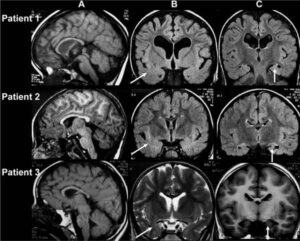

L'Encefalopatia traumatica cronica (CTE) e' stata fino ad oggi diagnosticata soltanto attraverso l'autopsia. La malattia, che colpisce molti giocatori di...